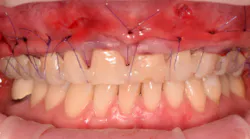

4. The surgical procedure is performed using a small gum-piercing instrument to create holes comparable with a laparoscopic procedure in medical surgeries. Four holes are usually enough to treat the entire arch (figures 11–12).

5. A full subperiosteal flap is then tunneled with appropriate instruments, and multiple A-PRF membranes are introduced inside the elevated tissue (figure 13). The gums are advanced toward the CEJ, and a tension-free flap release is performed and stabilized with sutures.

Coronally advanced flap (CAF) is maintained using an apical mattress suture (figure 14). Glycolon sutures 5.0 or 6.0 are the desired sutures to be able to maintain the flap in close contact with root proximity for at least three to four weeks.

This new biological approach involving blood derivatives A-PRF and I-PRF combined with precision minimally invasive surgery for root coverage demonstrates faster healing without the need of a donor site. The morbidity of GDT is decreased and patient case acceptance is higher compared with traditional grafts. Before-and-after pictures are shown below (figures 15–22).